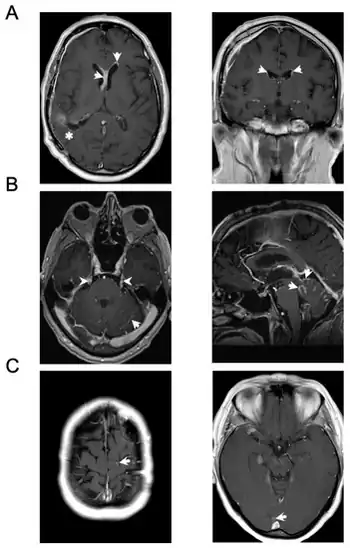

Screening involves an MRI scan to identify and diagnose tumors in the subarachnoid region of the brain. MRI can make a diagnosis even without an analysis of the cerebrospinal fluid but it can sometimes be difficult to detect because MRI scans cannot always pick up the problem.[21]

CSF examination is the most useful diagnostic tool for NM. Patients with suspected NM should undergo one or two lumbar punctures, cranial magnetic resonance imaging (MRI), spinal MRI, and a radioisotope CSF flow study to rule out sites of CSF block. If the cytology remains negative and radiological studies are not definitive, consideration may be given to ventricular or lateral cervical spine CSF analysis based on the suspected site of predominant disease. Consideration of signs, symptoms, and neuroimaging can help with the placement to where CSF is drawn. Median time of diagnosis from initial primary cancer diagnosis is between 76 days and 17 months.[23]

- MRI: Meningeal findings are described with the following characteristics: Nodular meningeal tumor, meningeal thickening >3 mm and a subjectively strong contrast enhancement. A smooth contrast enhancement of the meninges was judged to be typical for inflammatory, nonneoplastic meningitis.[24]